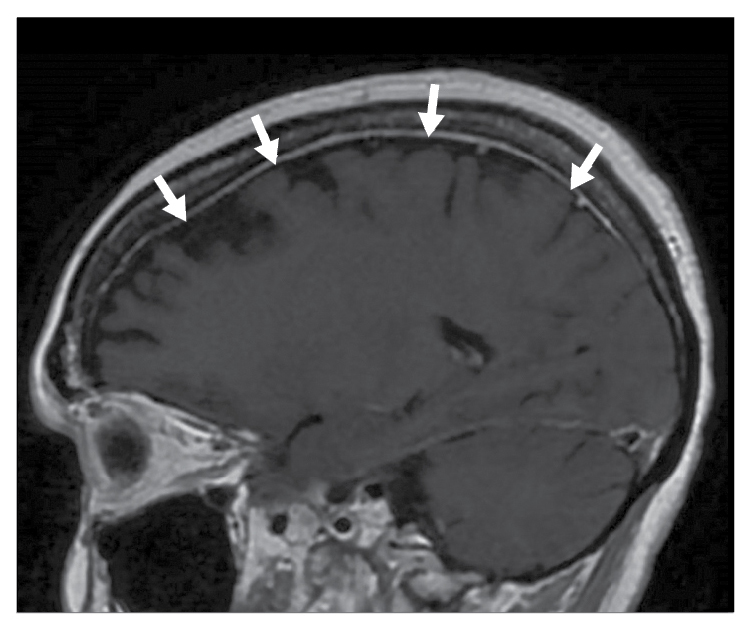

Positron emission tomography–computed tomography (PET-CT) scanning did not demonstrate 18F-fluorodeoxyglucose (FDG)-avid lymphadenopathy or evidence of occult malignancy. Magnetic resonance imaging (MRI) of the brain demonstrated bilateral convexity pachymeningeal thickening and enhancement (Fig. 2). Cerebrospinal fluid testing demonstrated a white blood cell count of 42/mm3 (91% lymphocytes), a red blood cell count of 8/mm3, and normal levels of glucose and protein. Bacterial, acid-fast bacilli, and fungal cultures were negative. However, both respiratory and cerebrospinal fluid PCR testing demonstrated the presence of enterovirus RNA. She received 2 g/kg intravenous immunoglobulin (IVIG) for treatment of chronic enterovirus infection, with outpatient monitoring of IgG levels every 6 weeks and IVIG replacement if less than 650 mg/dL. Within 3 months of discharge, she had symptomatic resolution and normalization of liver enzymes.

Figure 2: A sagittal T1-weighted image post intravenous (IV) gadolinium demonstrating mild bilateral convexity pachymeningeal thickening and enhancement (white arrows).